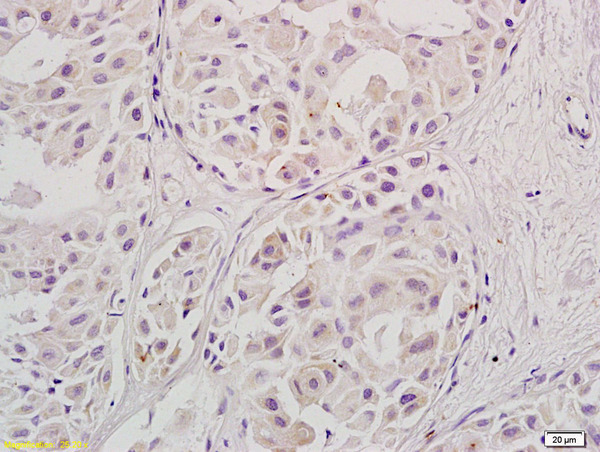

Supportive validation

- Submitted by

- Bioss (provider)

- Main image

- Experimental details

- Formalin-fixed and paraffin embedded human ovary carcinoma labeled with Anti-Stra8, Unconjugated (bs-1903R) at 1:800, followed by conjugation to the secondary antibody and DAB staining.

- Sample type

- Human

- Other comments

- Ovarian